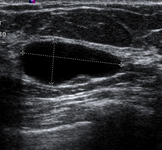

Ultrasonographic image of a simple cyst

Courtesy of Dr Lane Roland, University of Louisville; used with permission